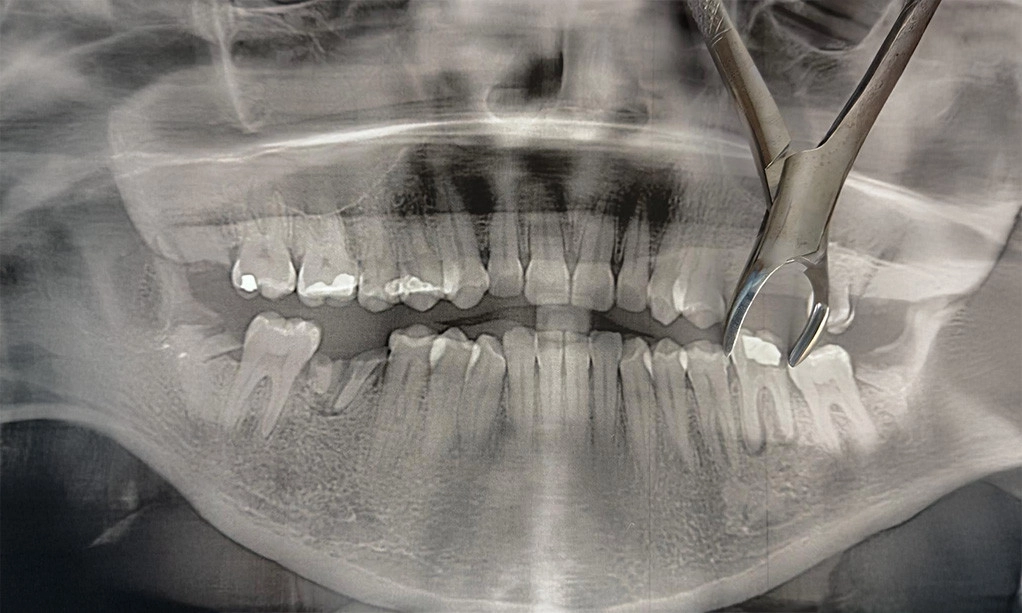

No one really gets excited about losing a tooth. But sometimes, pulling a tooth is the best decision; not because it's ideal, but because it prevents bigger problems later on. It’s less about doing something drastic and more about stepping in at the right moment before things get worse.

Extractions, whether due to discomfort, illness, or congestion, are more frequent (and less frightening) than most people realise. The most important thing is to do the process with clarity, care, and a calm, well-informed attitude.

Although teeth are powerful, they are not unbeatable. Leaving one in place when it is too broken or compromised to repair might result in more significant problems, such as spreading infection, altering bite alignment, or ongoing pain. Typically, extractions are advised in the following circumstances:

• A tooth that’s deeply decayed or fractured beyond repair

• Ongoing infection that hasn’t responded to root canal therapy or antibiotics

• Making space before orthodontic treatment or preparing for implants

• Wisdom teeth that are impacted or causing pressure on nearby teeth

• A break that extends below the gum line, leaving no surface to restore

These decisions aren’t made lightly. Before suggesting removal, a thorough evaluation is always done, and alternatives are discussed openly. It's not a rushed or routine call. It’s a choice made with your long-term health in mind.